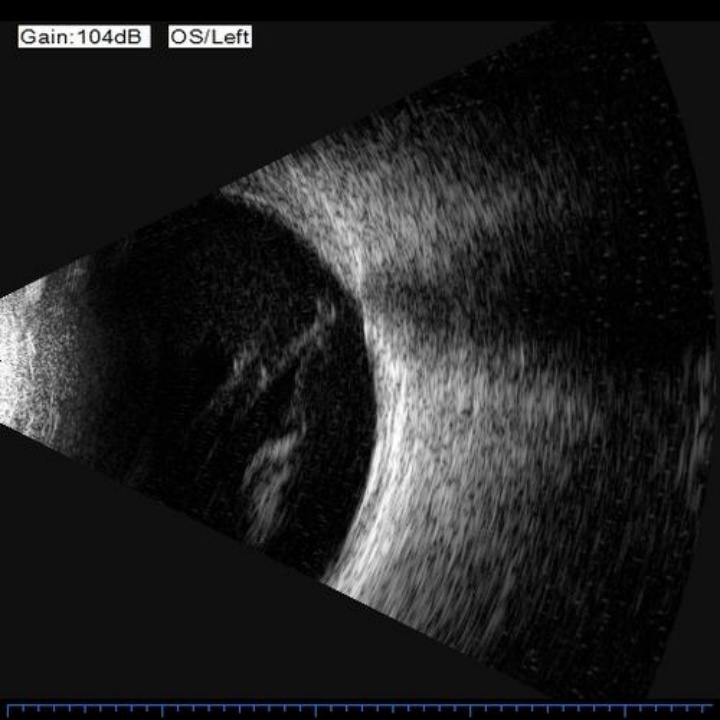

左眼术前B超图像,玻璃体积血

于先生今年60岁,患糖尿病多年,平时血糖控制不佳。左眼视力下降2年、骤降1周后,到同济大学附属同济医院眼科就诊。门诊医师检查发现,于先生左眼仅能看见物品在眼前晃动(手动视力),玻璃体内大量积血,视网膜已看不清,而右眼视网膜前已见增殖膜形成,散在出血点及渗出,确诊为双眼糖尿病性视网膜病变增殖期。

随后,同济医院眼科团队为其制定了手术方案:左眼玻璃体切割术+玻璃体硅油填充+视网膜激光光凝术,由于糖网病较为严重,术中视网膜血管渗血较多,故施行硅油填充,压迫出血点,并进行了充足的视网膜激光光凝,减少血管渗漏、封闭视网膜内异常的血管。术后于先生定期规律复诊,左眼眼底情况平稳。在3个月后,医生为于先生进行了左眼硅油取出术,将硅油最大程度取净,视力手动提升至0.05。